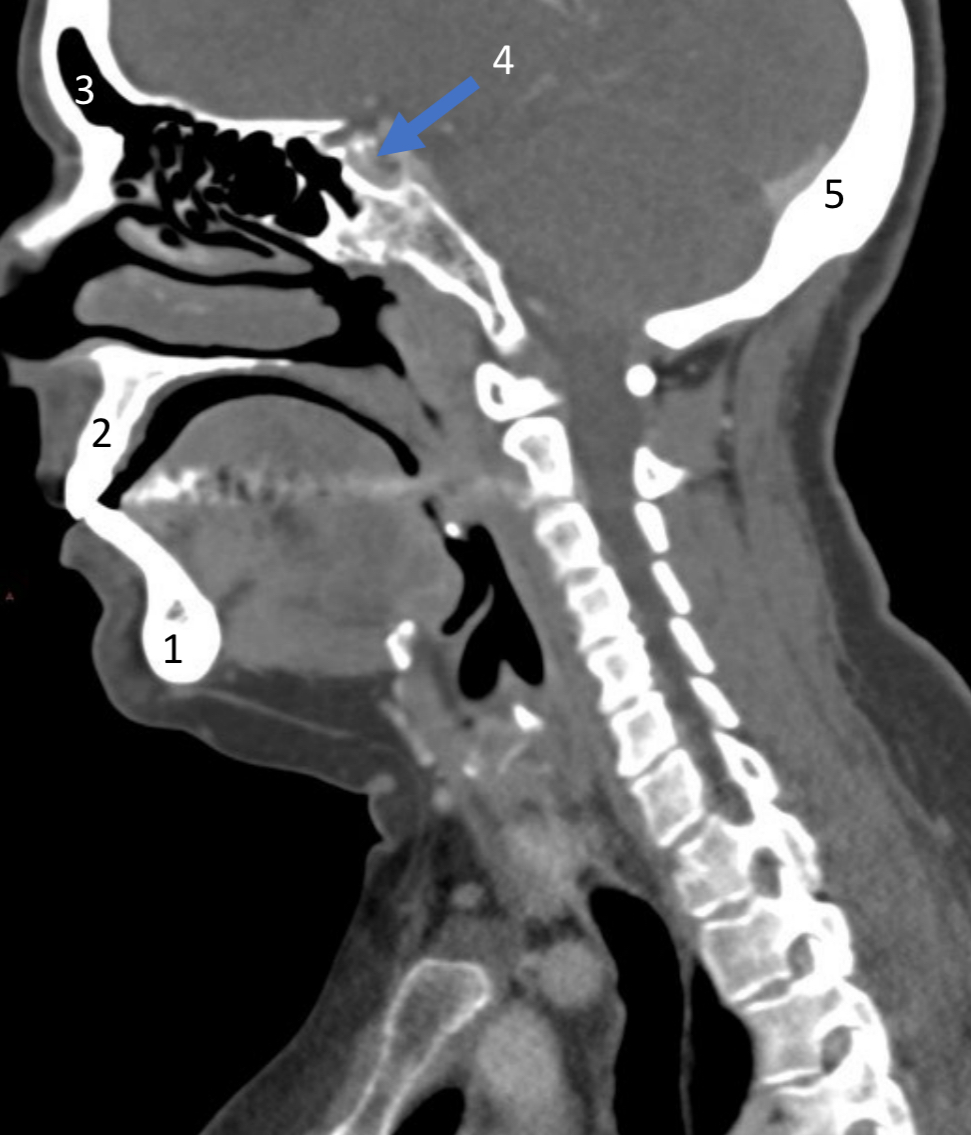

Mandible

ID bone

Maxilla

ID bone

Frontal sinus

ID structure

Pituitary fossa

ID structure

Occipital

ID bone

Lambdoid suture

ID structure

Frontal sinus

ID structure

Orbital margin

Orbit

Maxillary sinus

ID structure

Mandibular condyle

ID structure

Inferior nasal concha

ID structure

Hard palate

ID strucutre

Gonial angle

ID strucutre

Petrous ridge

ID structure

Groove of middle meningeal a.

ID structure

Roof of orbit

ID structure

Frontal sinus

ID structure

Pituitary fossa

ID structure

Petrous ridge

ID structure

Sphenoid sinus

ID structure

Hard palate

ID structure

Mastoid air cells

ID structure

Zygomatic arch

ID structure

Mandibular condyle

ID structure

External auditory meatus

ID structure

Mastoid air cells

ID structure

Foramen magnum

ID structure

Foramen ovale

ID structure

Foramen spinosum

ID structure